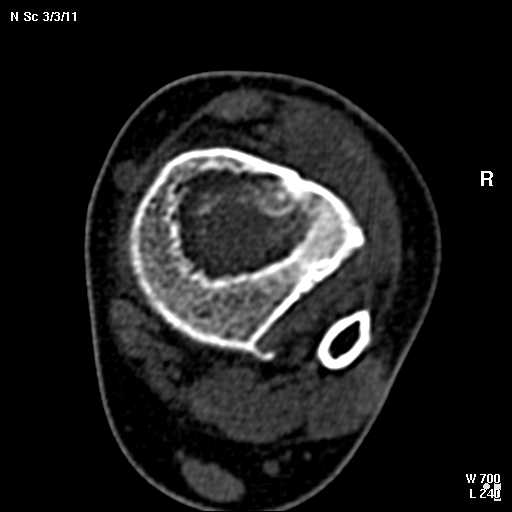

КТ изображения передаю на мой взгляд самые демонстративные. Их любезно записал коллега,

проводивший исследование в другом городе.

Прошу прощения за немного некоректную отправку КТ-снимков но по другому не получается :)